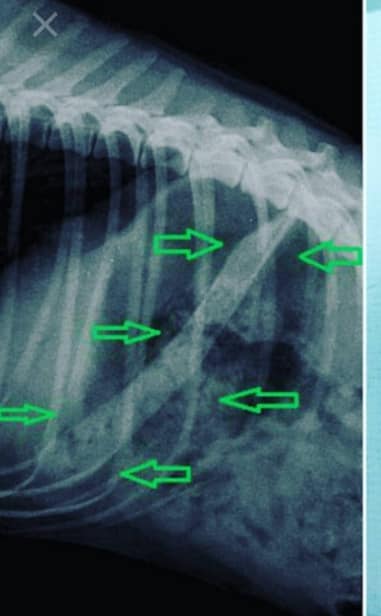

В итоге Жулю втроем, но таки поймали. Ее отвезли в ветклинику, которая была ближе всего. На кушетке из пасти собаки хлынула густая кровь. Как рассказывает Елена, было около трех литров. Оказалось, брюшное кровотечение.

- Такого объема и страшного состояния не видели даже врачи, – пишет волонтерка.